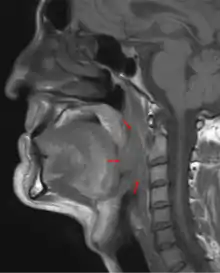

Oropharyngeal cancer,[1][2][3] also known as oropharyngeal squamous cell carcinoma and tonsil cancer,[1] is a disease in which abnormal cells with the potential to both grow locally and spread to other parts of the body are found in the oral cavity, in the tissue of the part of the throat (oropharynx) that includes the base of the tongue, the tonsils, the soft palate, and the walls of the pharynx.[1][2][3][5]

| 3D medical illustration showing the cancer formation in the tissues of the oropharynx | |